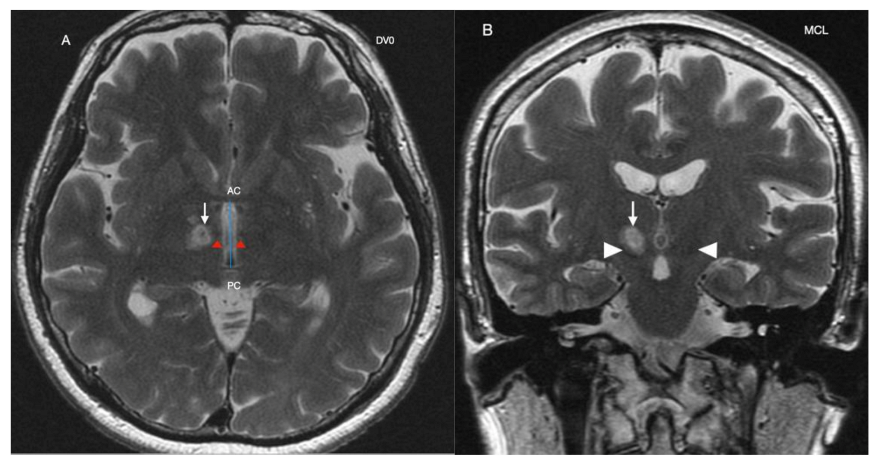

Procedure